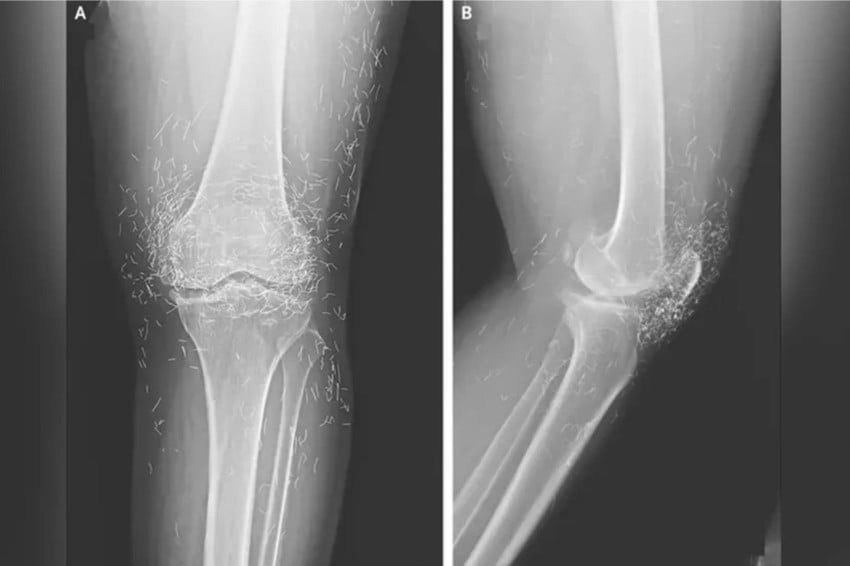

Viral! Dokter Temukan Ratusan Benang Emas Murni di Lutut Wanita Ini

loading… Sebuah peristiwa medis yang mengejutkan terjadi di Korea Selatan ketika tim dokter menemukan ratusan benang emas murni yang tertanam di lutut seorang pasien. Foto/Oddity Central JAKARTA – Sebuah peristiwa medis yang mengejutkan terjadi di Korea Selatan ketika tim dokter…